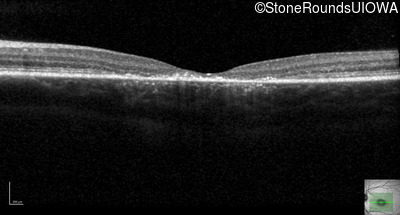

Optical Coherence Tomography - Left - 20/125 sc

Exemplar / OCT Stack

OCT Stack